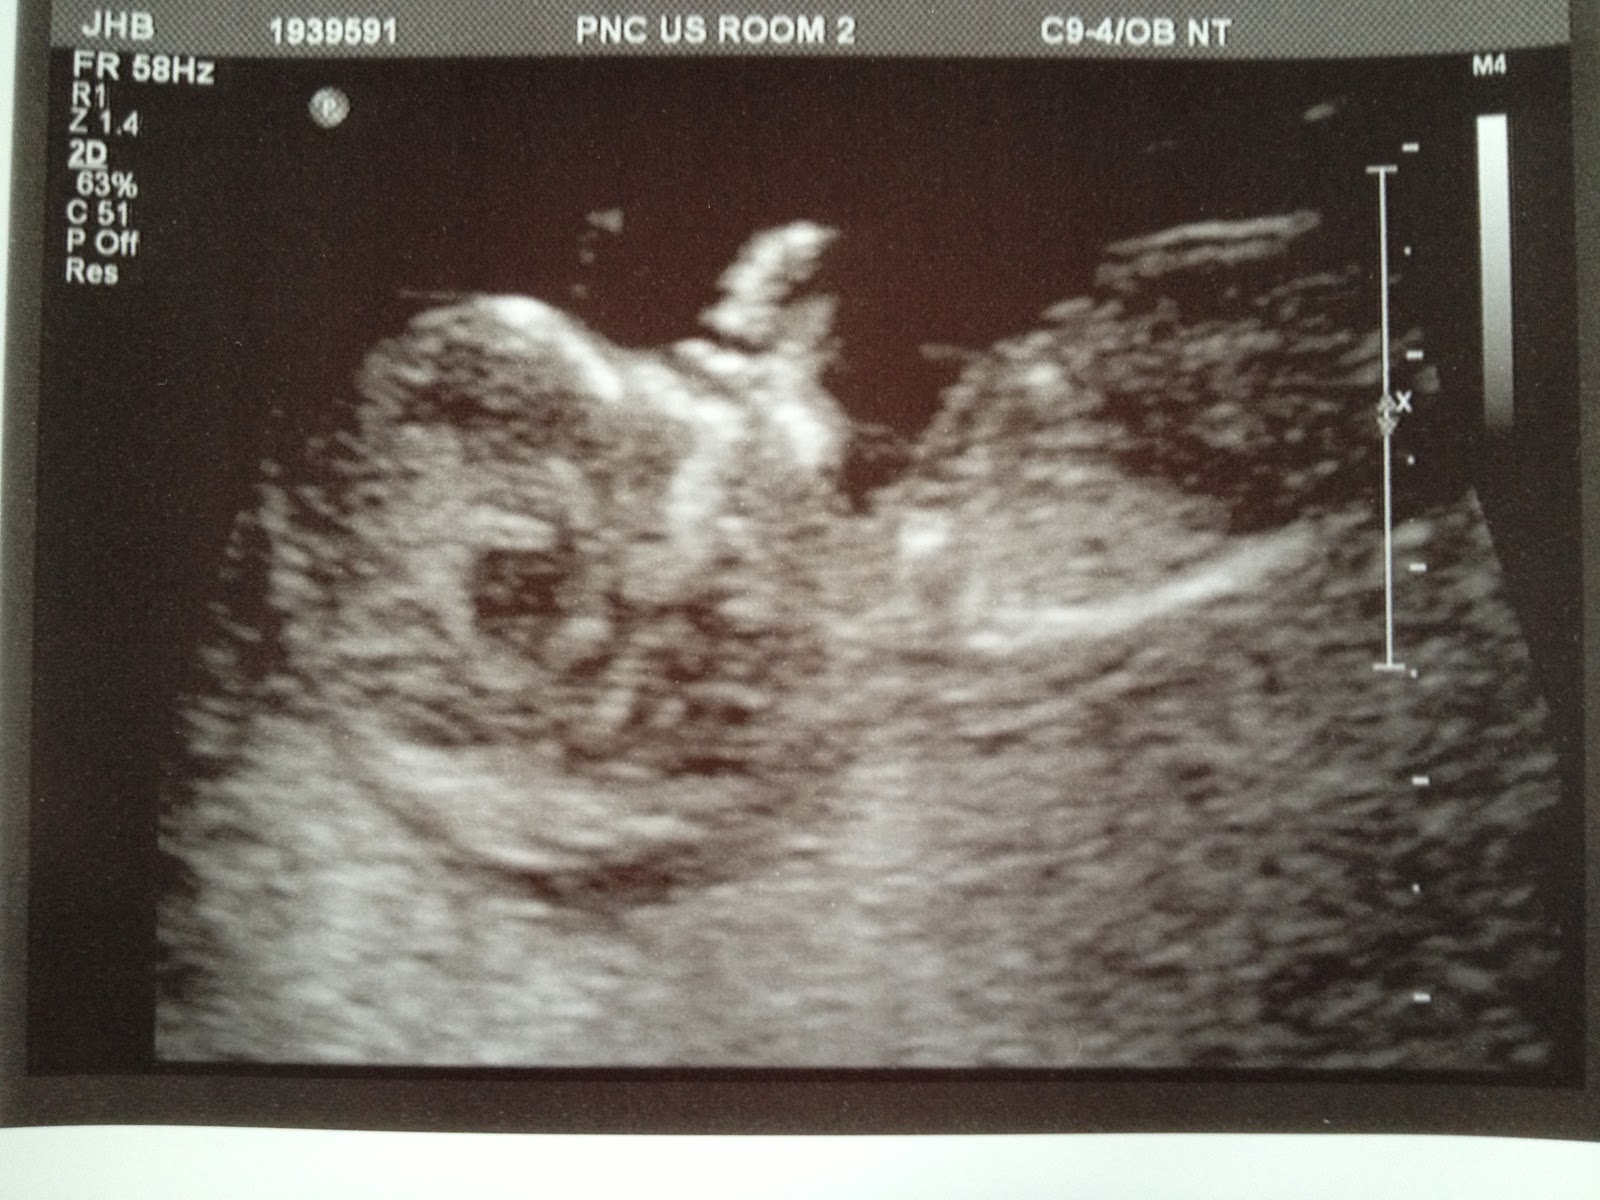

Our latest development in the baby saga is we had our first ultrasound last Tuesday. It was SO cool to watch it move around! It was so active!!! I was in awe seeing it's little skeleton moving about, and seeing it look straight on with a skeletal smile :) Watching the blood flow and it's little heart beat was probably the coolest thing so far. The girls at work call it my little sea monkey. My husband has taken to calling it "Predator" I like to think of it as my little monster. (hopefully it's not born with a tail though)

Can you believe that hand?! I kept asking questions like, "Why is the brain so small and not taking up the entire cavity?" My husband's response? "It's definitely a Webb, big head, little brain." The tech, "because it's still growing." Ok, so it's normal. (sigh of relief) Is it sucking it's thumb?! apparently it can't suck yet at 12 weeks, but boy is it trying. I have never been so in awe, so proud, and so in love for anything else in my life. I still can't believe how amazing the human body is. Thankfully, it's smarter than I am and I feel good that it can do it's thing on auto pilot. All I have to do is eat healthy, exercise and keep whispering sweet nothings to this little parasite. <3